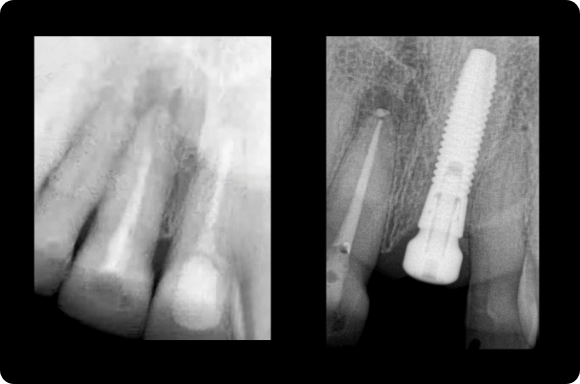

This mastery-level course discusses both the prevention and management of surgical and restorative complications. Within the surgical realm, the presentation focuses on early implant failure and later peri-implant disease. Prosthetic concepts will involve preventative prosthesis design, screw/abutment removal, and sequencing that acknowledges the importance of patient experience.

The implant curriculum is an interactive, procedure-based series of courses that use individual cases to teach current implant treatment. This approach is in contrast to conventional dental education that focuses more on didactic topics and theory. The purpose of using this educational approach is to highlight the patients and procedures found in everyday clinical practice, where the most important concepts are observed and discussed in multiple clinical scenarios.